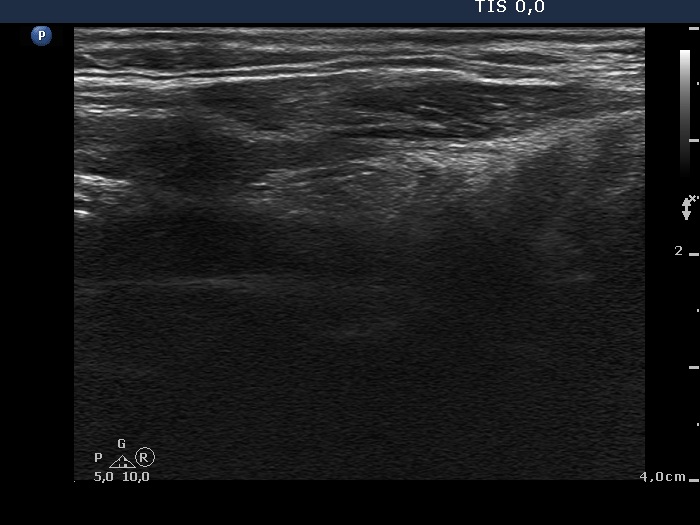

TIRADS - case cons100_018 (ultrasonographic picture 5)

Left lobe, longitudinal scan.